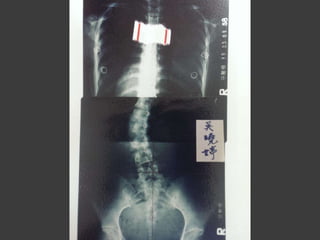

脊椎神經對身體健康的影響

人體很多疾病源於脊椎骨的位

置不正所造成

脊椎骨旁密布脊椎神經,是人

體的神經樞紐

脊椎不正

脊椎骨不正日積月累,

對自身造成莫大傷害而不自知